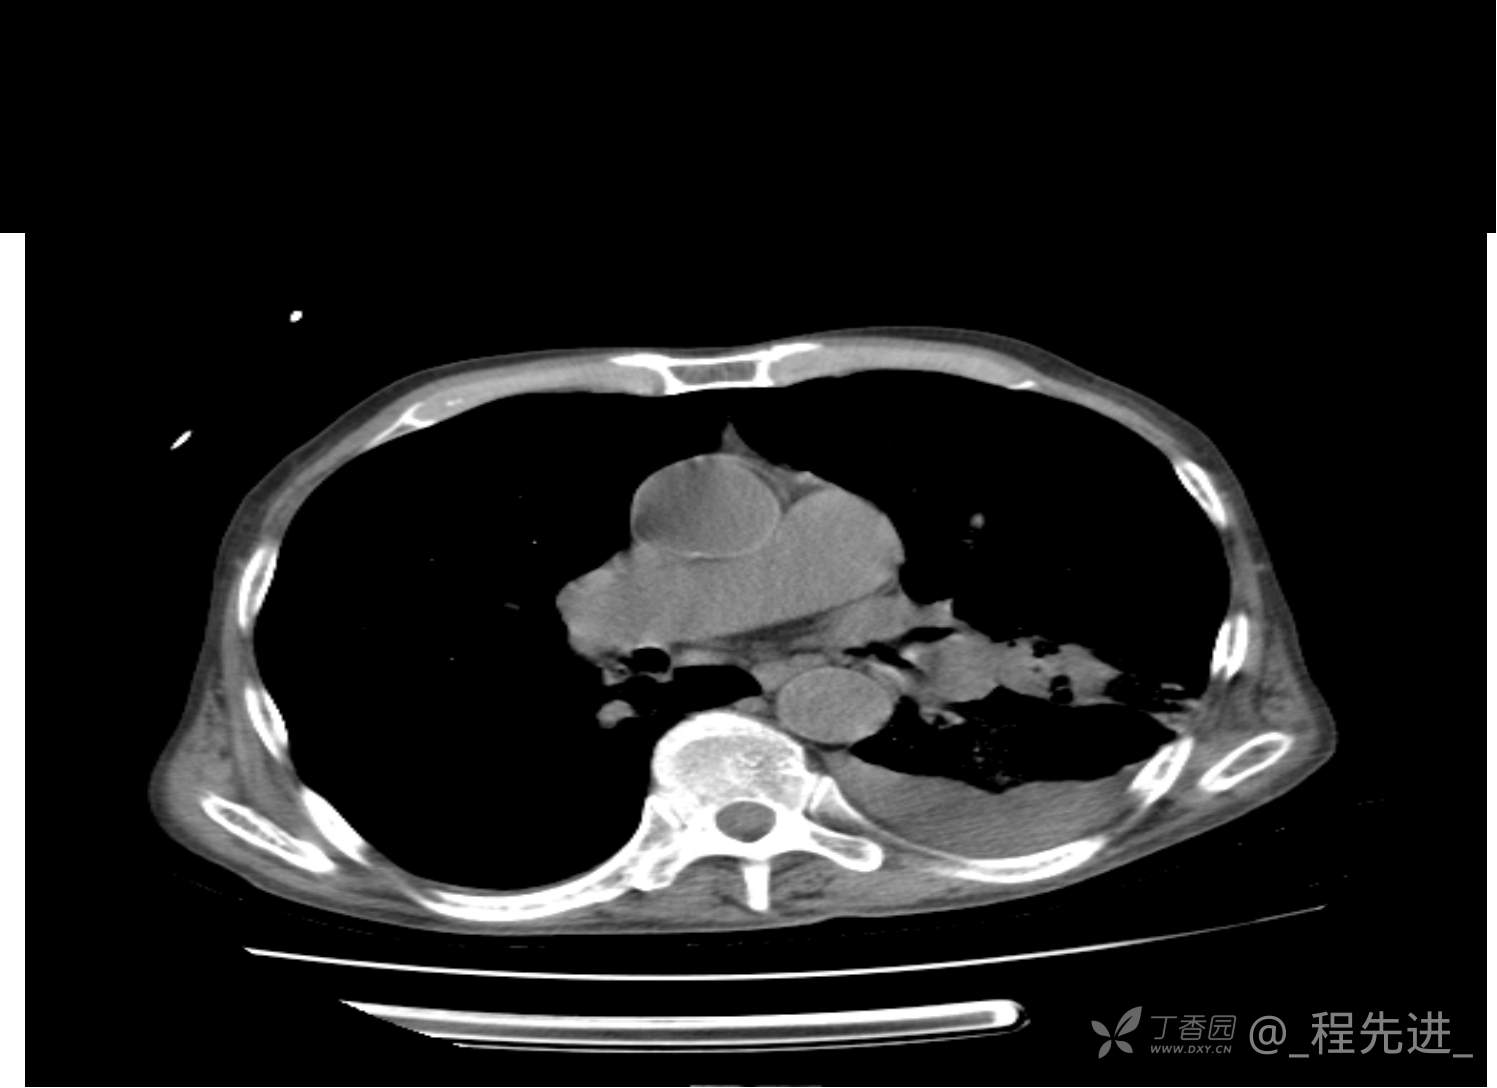

患者性别:男

患者年龄:81岁

简要病史:反复咳嗽、咳痰20余年,加重1周。两肺呼吸音低,可闻及散在干湿啰音。